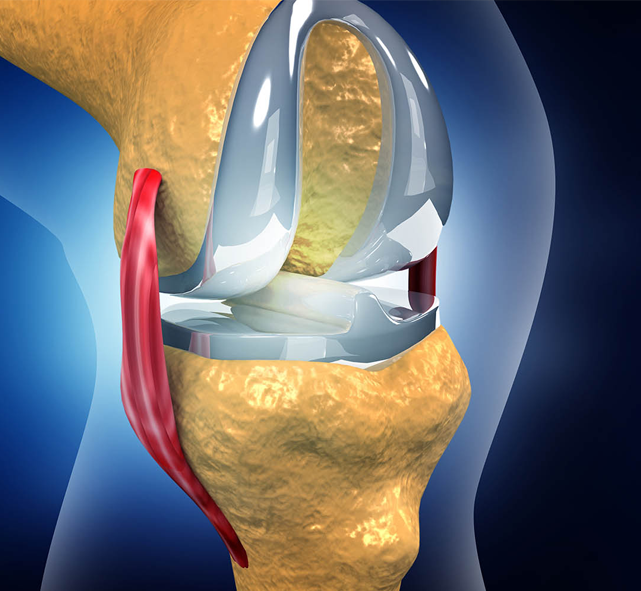

Anatomy

- Maltracking of the Patella

When the kneecap moves improperly within its groove, it can irritate the cartilage and surrounding tissues, causing pain and inflammation.

- Clinical Examination:Assessing muscle strength, knee alignment, and patellar tracking.

- MRI:For detailed evaluation of the cartilage, soft tissues, and patellar alignment.